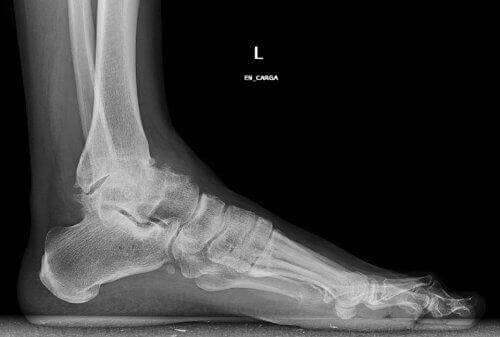

Osteoartrit i fotleden är något som begränsar mångas livskvalitet. Det är en tyst och varaktig sjukdom som begränsar rörelsefriheten. Smärtan försvinner heller inte alltid när man tar smärtstillande.

Även om många mest pratar om nedbrytning av höfter och knän är fotleden också en kroppsdel som ofta är väldigt utsatt för osteoartrit.

Den här typen av artros beror på varaktigt slit på brosket i fotleden. Det är vanligt att den blir stel och utvecklar deformiteter med åldern.

Klassiska osteofyter kan också uppkomma, vilket gör det till en väldigt smärtsam och begränsande åkomma.